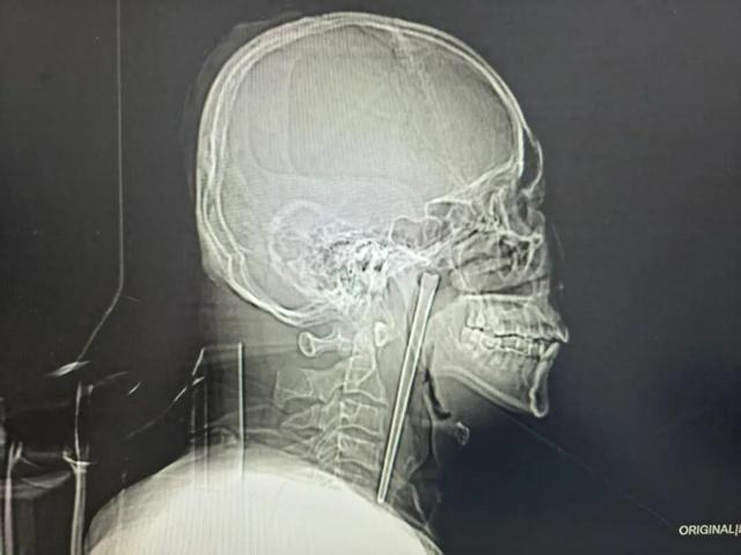

X-ray image showing the metal foreign object lodged in the man's throat. Photo: Baidu |

Examinations revealed the metal chopstick was deeply embedded in the patient's soft palate. Fortunately, the surrounding mucous membrane was not severely damaged, and nearby organs were not displaced. Doctors confirmed the patient's vocal cords were functioning normally. Since Mr. Wang declined open neck surgery, doctors devised a minimally invasive plan to remove the foreign object orally. The surgery proceeded smoothly with minimal blood loss. The 12 cm metal chopstick was successfully extracted. Mr. Wang recovered well and was discharged a few days later.